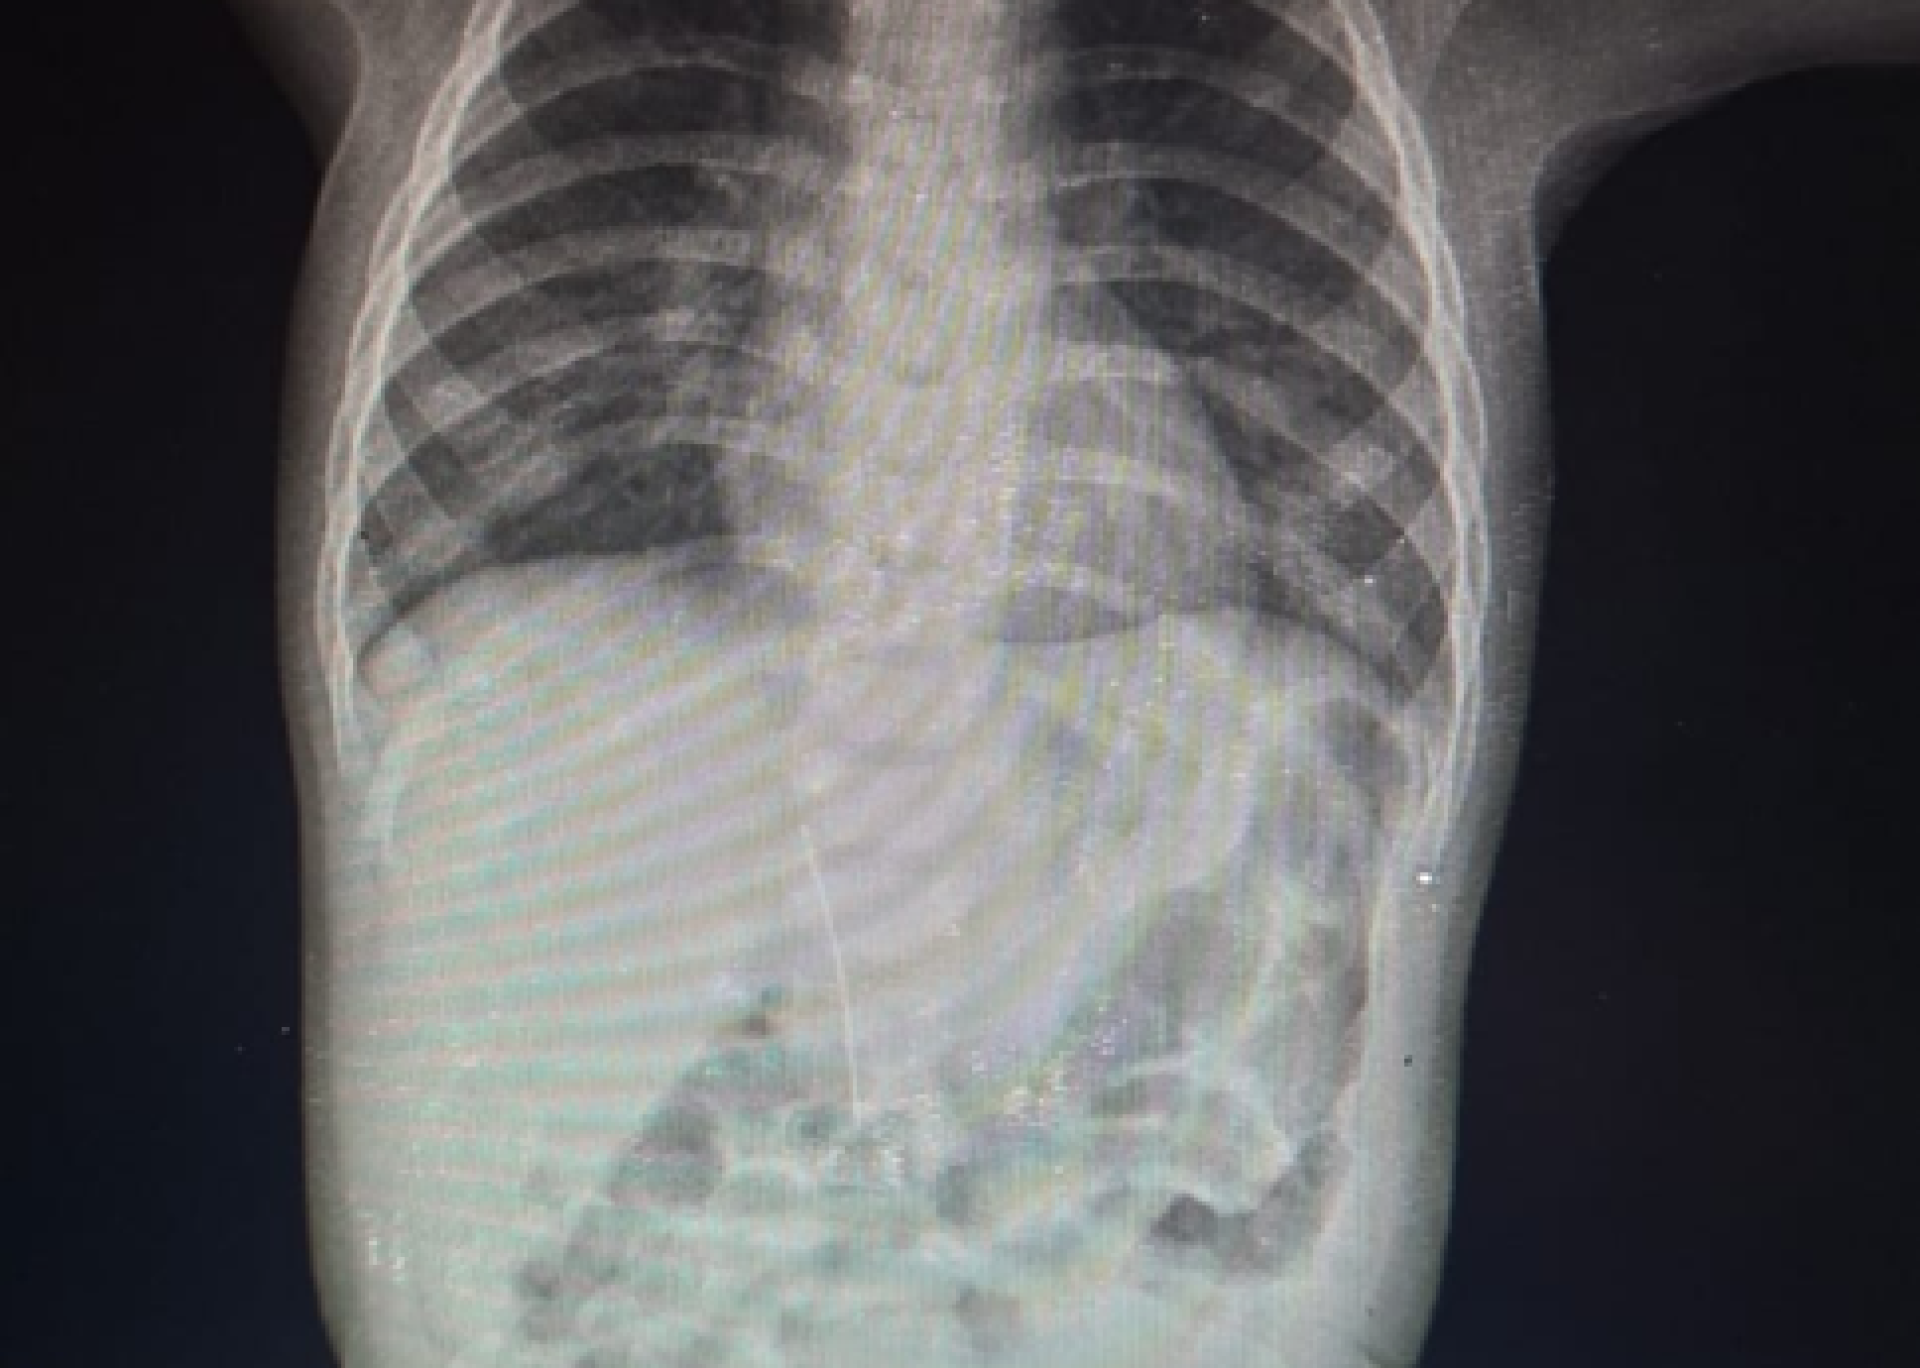

В Туркестанской области врачи обнаружили иглу в теле 8-месячного ребёнка, который был госпитализирован с подозрением на краснуху. При проведении рентгенологического исследования в брюшной полости малыша была выявлена инородная игла, что стало причиной его беспокойства и повышения температуры.

Как выяснили медики, игла не попала в организм через пищеварительный тракт, а проникла со стороны печени. Мать ребёнка отметила, что малыш не мог самостоятельно проглотить её.

Фото предоставлено управлением здравоохранения региона.